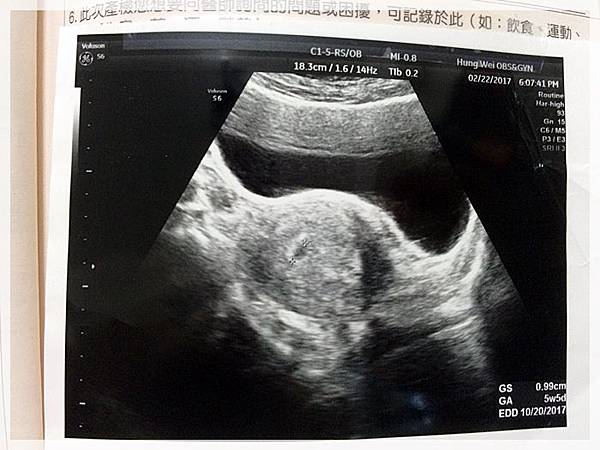

這是第一次產檢時的超音波相片...

這是第二次產檢時的超音波相片...

這是第三次產檢也就是這次產檢時的超音波相片...

歡迎你的到來...樂樂![]()